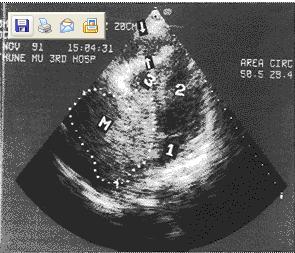

| 超聲心動圖心房顯著擴大 | 不常見 | 常見 |

| 舒張早期二尖瓣血流速率 | 有明顯的呼吸變化 | 隨呼吸變化極小 |

| 彼此相反的心室充盈 | 有 | 無 |